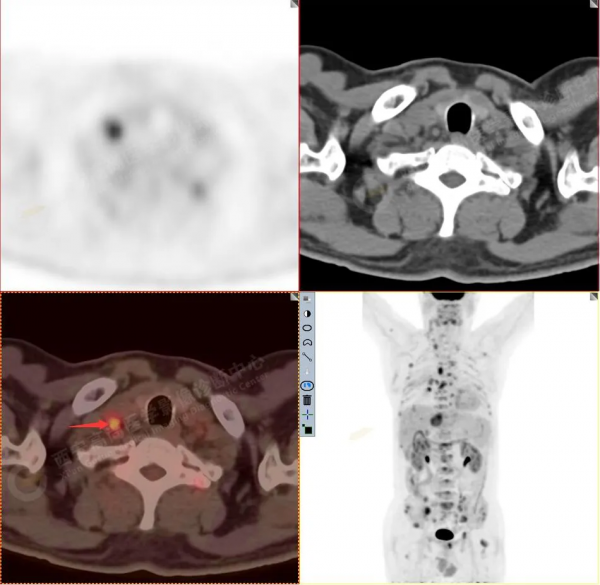

2.以下為部分全身多發轉移灶

3.右側肺門、縱隔(1L、1R、3A、4、6、7組)及雙側鎖骨上多發腫大淋巴結,呈不同程度FDG代謝異常增高,考慮為淋巴結轉移。

5.腰4椎體左側緣溶骨性骨質破壞,FDG代謝異常增高,考慮骨轉移瘤。